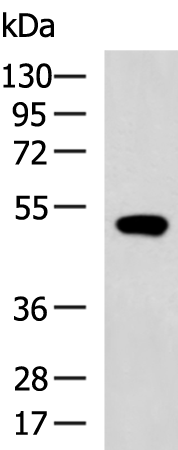

分类: 科研抗体货号: P06438别名: ENT2; DER12; HNP36应用: WB,IHC反应种属: Human